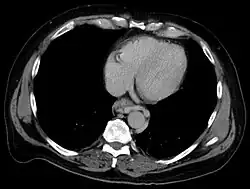

Esophageal varices are extremely dilated sub-mucosal veins in the lower third of the esophagus.[1] They are most often a consequence of portal hypertension,[2] commonly due to cirrhosis.[3] People with esophageal varices have a strong tendency to develop severe bleeding which left untreated can be fatal. Esophageal varices are typically diagnosed through an esophagogastroduodenoscopy.[4]

The upper two thirds of the esophagus are drained via the esophageal veins, which carry deoxygenated blood from the esophagus to the azygos vein, which in turn drains directly into the superior vena cava. These veins have no part in the development of esophageal varices. The lower one third of the esophagus is drained into the superficial veins lining the esophageal mucosa, which drain into the left gastric vein, which in turn drains directly into the portal vein. These superficial veins (normally only approximately 1 mm in diameter) become distended up to 1–2 cm in diameter in association with portal hypertension.

Normal portal pressure is approximately 9 mmHg compared to an inferior vena cava pressure of 2–6 mmHg. This creates a normal pressure gradient of 3–7 mmHg. If the portal pressure rises above 12 mmHg, this gradient rises to 7–10 mmHg.[5] A gradient greater than 5 mmHg is considered portal hypertension. At gradients greater than 10 mmHg, blood flowing through the hepatic portal system is redirected from the liver into areas with lower venous pressures. This means that collateral circulation develops in the lower esophagus, abdominal wall, stomach, and rectum. The small blood vessels in these areas become distended, becoming more thin-walled, and appear as varicosities.

In situations where portal pressures increase, such as with cirrhosis, there is dilation of veins in the anastomosis, leading to esophageal varices.[3] Splenic vein thrombosis is a rare condition that causes esophageal varices without a raised portal pressure. Splenectomy can cure the variceal bleeding due to splenic vein thrombosis.